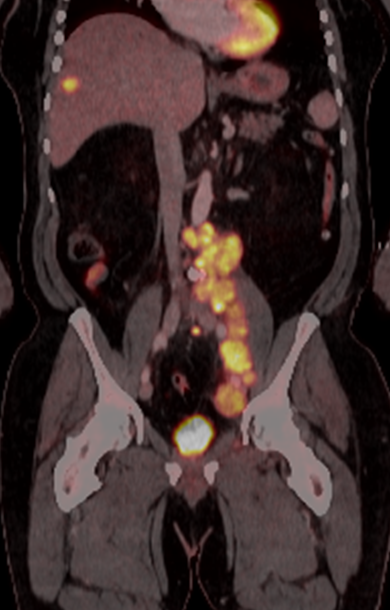

Aktuálny trend v zdravotnej starostlivosti je liečba presne na mieru pacienta – precízna medicína. Unikátne PET/CT skenery umožňujú v plnej miere tento trend naplniť aj na Slovensku. Bratislavská spoločnosť Biont je v rámci nukleárnej medicíny špecialistom na pozitrónovú emisnú tomografiu (PET). Nedávno spustila prevádzku revolučného PET/CT skenera Biograph Vision. Ide o prvú inštaláciu digitálneho PET/CT systému na Slovensku a zároveň predstavuje najmodernejší prístroj v tejto oblasti, ktorý bude poskytovať lepšiu, presnejšiu a šetrnejšiu starostlivosť pre pacientov z celého Slovenska. Hľadanie svietiacich bodov Biograph Vision vďaka jedinečnej digitálnej polovodičovej technológii SiPM detektorov je prístrojom s najdetailnejším zobrazením na trhu a s najvyššou účinnou senzitivitou. „Pomáha skrátiť čas skenovania a znížiť aplikovanú dávku rádiofarmaka. Znižuje tým nielen náklady na vyšetrenie, ale predovšetkým čas vystavenia pacienta radiačnej záťaži. Zároveň umožňuje zobraziť aj men ...Článok je uzamknutý